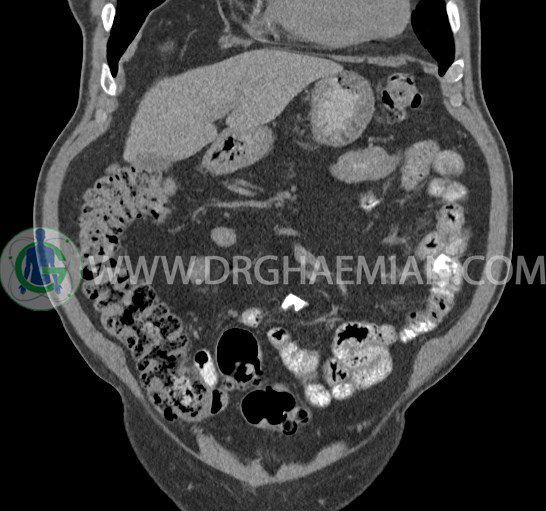

سی تی اسکن لگن یکی از روش های تصویربرداری با سی تی اسکن است. این روش با استفاده از تشعشعات تصاویر عرضی از ناحیه شکمی ایجاد میکند. در این کیس ديورتيكولوزيس، کیست های کورتیکال در هر دو کلیه، لنفادنوپاتی، کلسیفیکاسیون دیواره آئورت و شریان ایلیاک، تغییرات DJD ناحیه توراکولومبار و پروستات بزرگتر از عادی دیده می شود.

در سي تي اسکن اسپيرال شکم و لگن با و بدون کنتراست خوراکی و وريدی (مولتي ديدکتور 16 با مقاطع ظريف و بازسازي هاي ساژيتال و کرونال):

– کيست هاي کورتيکال ساده به قطر 5 mm تا 50 mm در کليه راست و به قطر 5mm تا 55 mm در کليه چپ

– توده ايزودنس به ابعاد mm 17 x 28 در پره ائورت مجاور قسمت تحتاني D3 دئودنوم مطرح کننده لنفادنوپاتي و با احتمال کمتر آنوريسم ترومبوزه (نيازمند مطابقت سونولوژيک)

– کلسيفيکاسيون ديواره آئورت و شريان ها ايلياک همراه با نشانه هاي ترومبوز مورال در بيفورکاسيون ائورت با امتداد به پروگزيمال هاي شريان هاي ايلياک

– ديورتيكولوزيس در کولون نزولي وسيگموئيد

لنفادنوپاتي به ابعاد mm 22 x 25 مجاور شريان ايلياک خارجي چپ و به ابعاد mm 17 x 28 مجاور شريان ايلياک خارجي راست

– تغييرات DJD در ناحيه توراکولومبار و

– پروستات به ابعاد mm 45 x 54، بزرگ تر از نرمال

مشهود است.